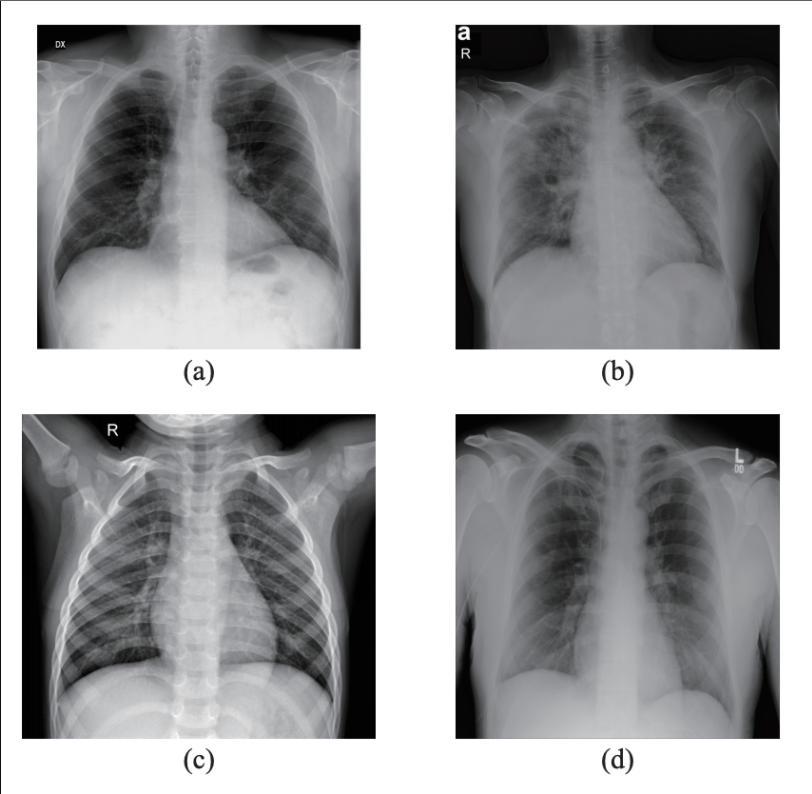

This photo gallery shows the variety of radiological presentations of COVID-19 (SARS-CoV-2) in medical imaging, including computed tomography (CT), radiograph X-rays, ultrasound, echocardiograms and magnetic resonance imaging (MRI). The radiology images show examples of typical COVID pneumonia in the lungs and the numerous complications the virus causes in the body in multiple organs, including the brain, kidneys, heart, abdomen and vascular system.

Ultrasound, especially hand-held ultrasound imaging devices, have become a primary imaging modality for novel coronavirus because of the ease to bag the device and sterilize it after use. CT and mobile X-ray systems are also used as front-line imaging systems for COVID-positive or suspected COVID patients.